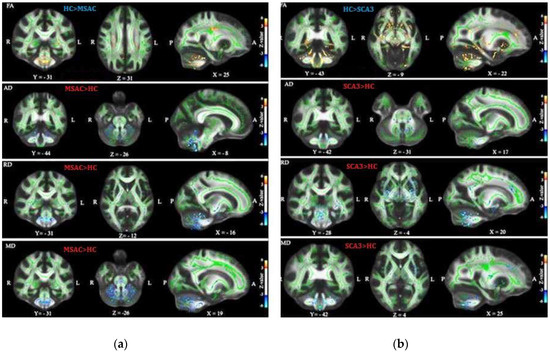

3.1. Patients with SCA3 or MSA-C Demonstrated Significant Decrease in FA and Increase in AD, RD, and MD